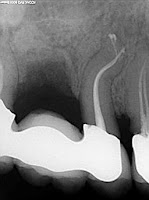

Internal Resorption -b: یک شکل غیر

معمول ذوب دندانی است که از قسمت وسطی دندان آغاز شده و بیشتر ناشی از التهاب پولپ

میباشد. فضای داخلی کانال دندان بشکل بیضوی (Oval) وسعت پیدا

میکند. این حادثه بیشتر در دندانهای سنترال علوی اتفاق می افتد ولی میتواند در هر

دندان دیگر واقع شود. در رادیوگرافی، جدار کانال خفیفاً توسعه یافته بنظر میرسد.